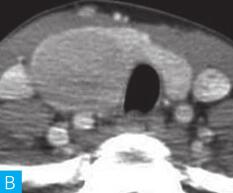

图2 滤泡性腺瘤:A.颈部CT横断面;B.颈部CT横断面增强

(2)滤泡细胞癌:

多单发,呈圆形或椭圆形,包膜厚而不均,可以发生钙化,表现为厚壁环状钙化,钙化常不连续;增强后,肿瘤内部常因血栓形成而强化程度低于周围甲状腺组织,呈低强化表现(图3),尤其是中央呈星芒状的低强化对于滤泡细胞癌的诊断具有重要价值。尽管部分滤泡细胞癌具有一定影像学特征,但大部分滤泡细胞癌仍缺乏特征性的影像学表现,其与滤泡性腺瘤和结节性甲状腺肿只能通过组织学进行鉴别。

图3 滤泡细胞:A.颈部CT横断面;B.颈部CT横断面增强